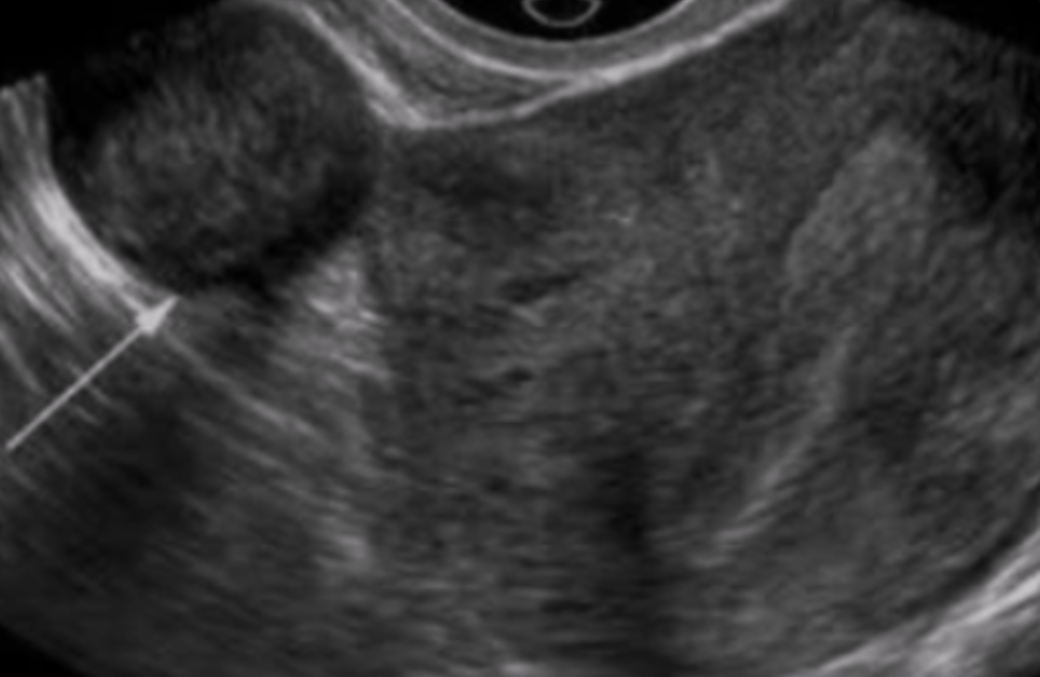

What type of fibroid is depicted in this image?

A. Intramural

B. Submucosal

C. Subserosal

D. Pedunculated

Intramural